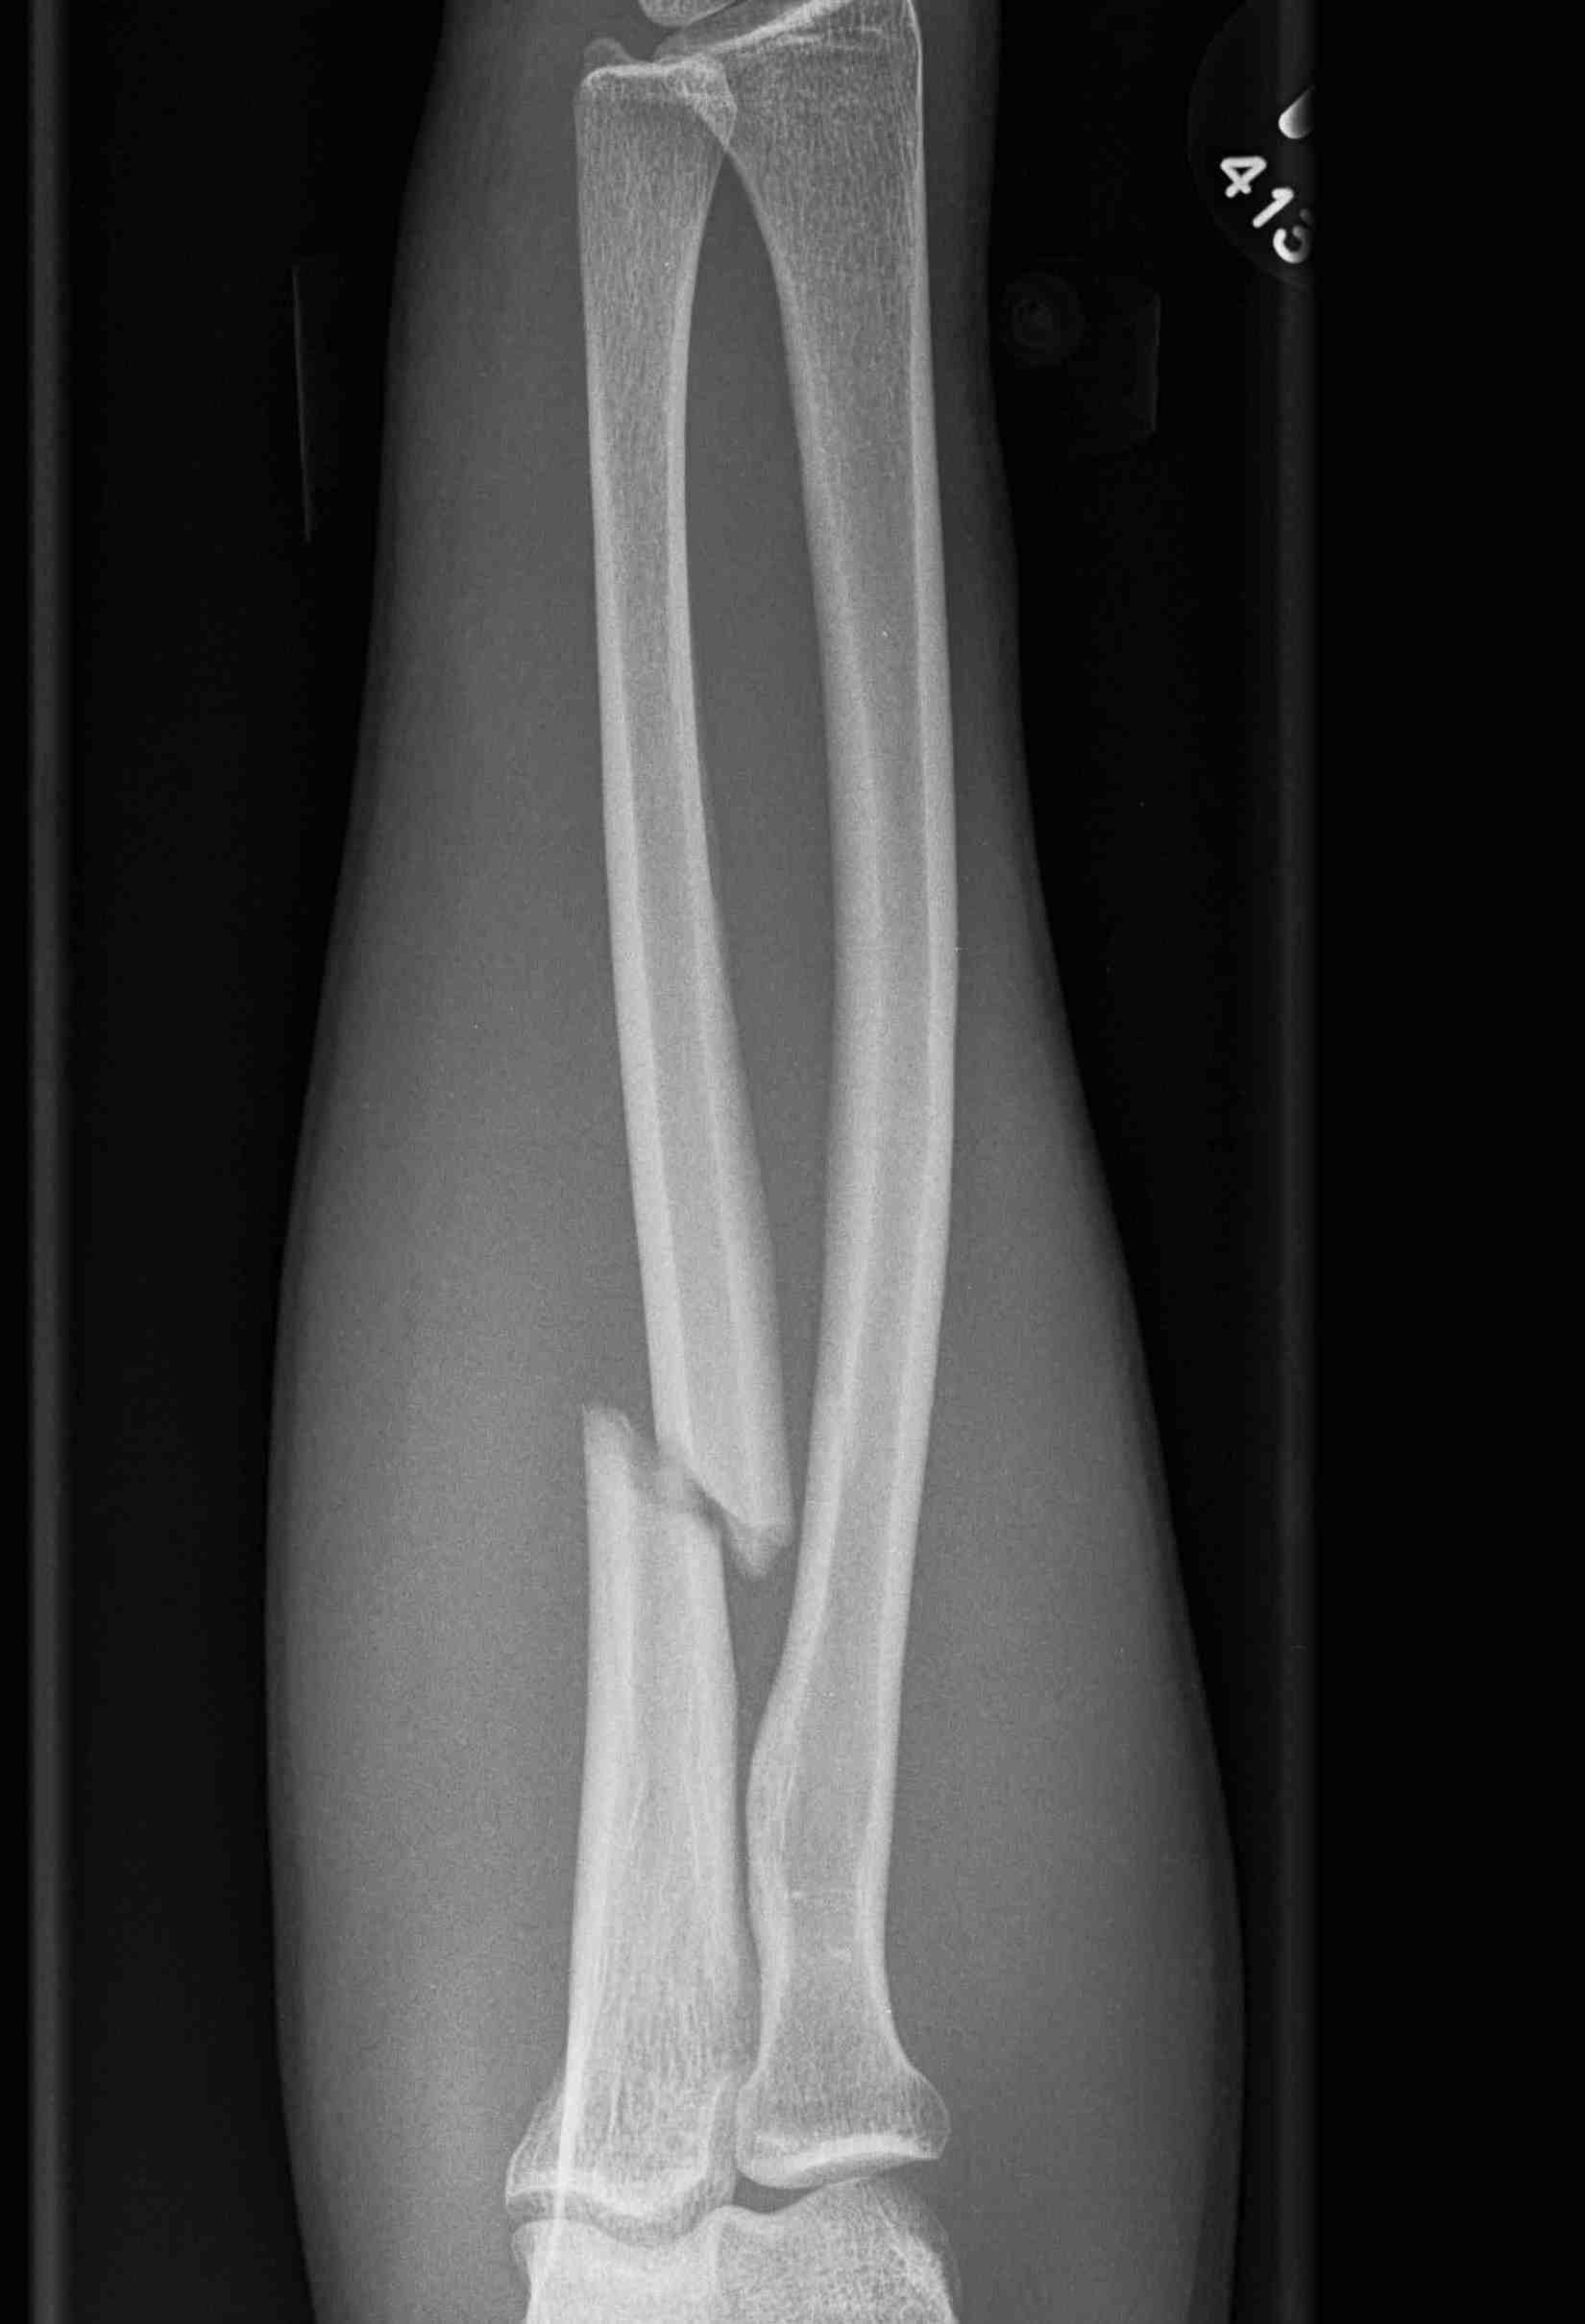

Options

Compression plating

Intra-medullary nail

Ulna Intramedullary WireUlna Plating

Results

Gaume et al Injury 2020

- IM K wire v plate in 54 patients

- 3 nonunions with plate, none with IM wire

- 70% of patients required wire removal

- 11% of patients required plate removal

Complications

nonunionnonunion

Ulna nonunion after plating